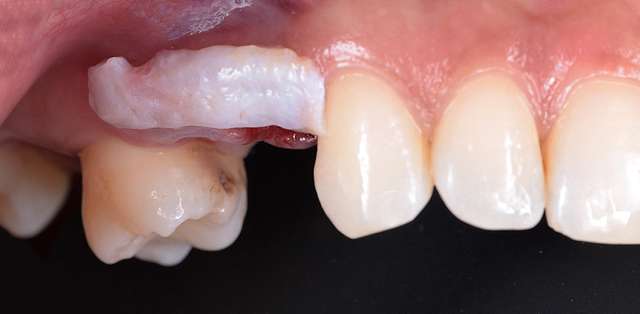

Chirurgia ghidata, ne faciliteaza o pozitie ideal pre-planificata, care nu tine cont doar de os, ci si de o pozitie optima in relatie cu viitorul dinte.Chirurgia ghidata înseamnă o precizie crescuta, care inseamna siguranta mai mare, timp operator mai scazut, si trauma mai mica. De asemenea focusul in acest tip de interventii a migrat spre reconstructia tesuturilor, care e pe termen lung are un impact mult mai mare atat estetic cat si biologic, inserarea implantului in sine fiind trivializata de folosirea ghidului chirurgical. Cazul de fata este un exemplu al acestui tip de abordare.